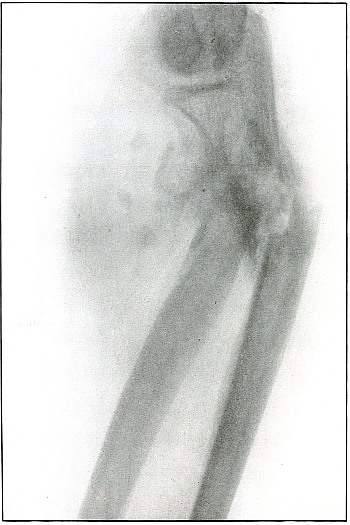

Plate 59.

_

[Pg 129]

Rifle—Plate 59.

LOWER EXTREMITY.

Gunshot Wound of the Left Knee-Joint,

with Lodgment of the Missile in the Joint.

The course of the bullet was transverse, entering the capsule posterior to the patella without injury to the bone.

As its shadow projection is almost circular, the bullet must be standing almost on its end pointing toward the plate with its long axis almost parallel to the line of projection.

As the fibular side of the leg lay next to the plate and as the only slightly enlarged shadow of the bullet indicates it to be near the plate, its position is in the joint near the fibular side.

As the bullet is undeformed and its penetrating power very slight, its velocity was that of extreme range.

The emergency treatment, is, of course, a simple antiseptic dressing with the leg held in the most comfortable position by muscular action.

The subsequent treatment is removal of the bullet when proper surgical conditions obtain. [Pg 130]